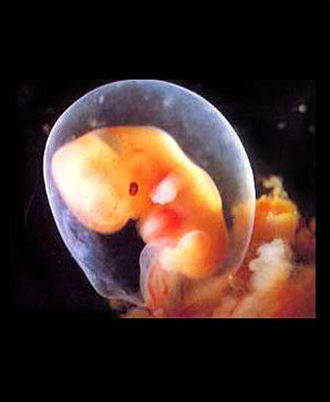

- 임신 증상진단

- 뚜렷한 임신증상이 없을 수 있습니다.

증상:입덧, 피로, 빈뇨, 두통 등 - 임신확인 검사

배란일로 보터 일주일 이후가 되면 임신테스트기로 임신사실이 확인됩니다.